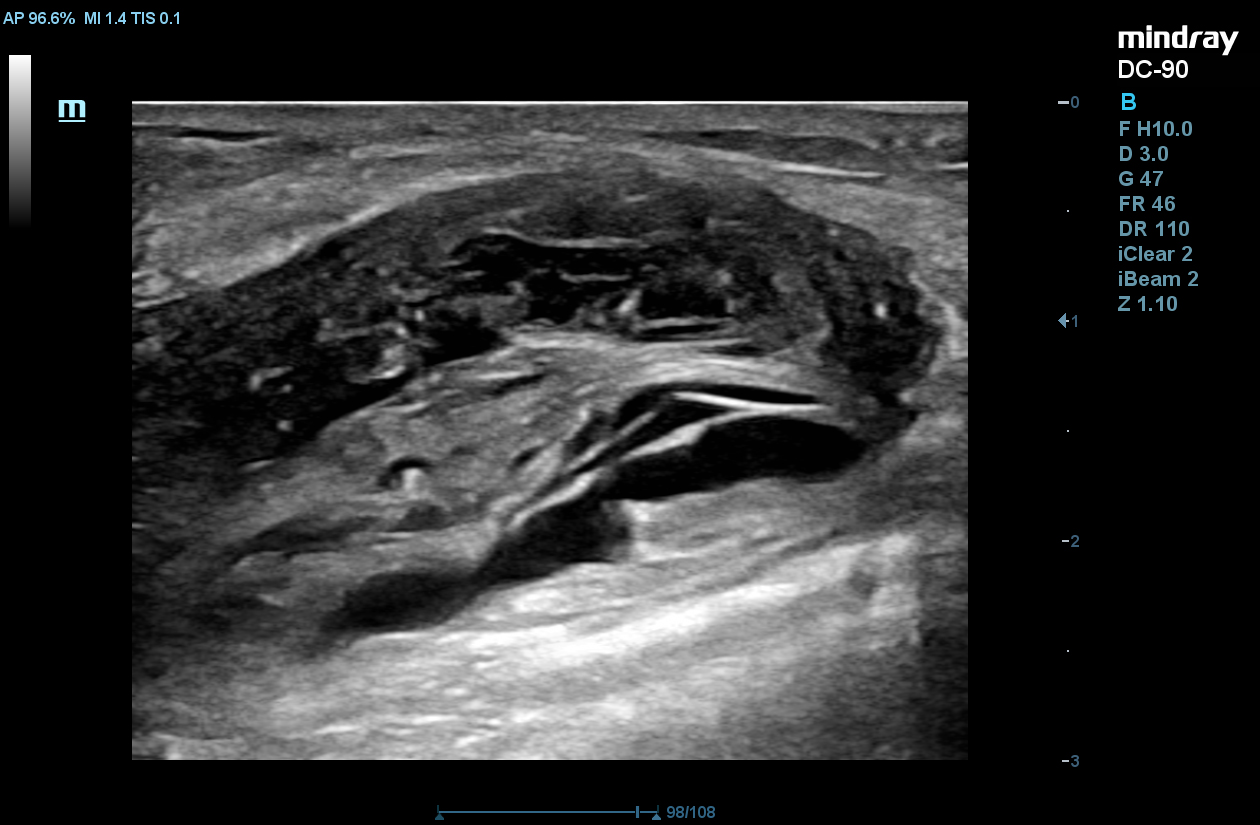

STE

Mindray’s Sound Touch Elastography (STE) utilizes exclusive Ultra-Wide Beam Tracking technology to provide comprehensive quantification metrics and dynamic visual display of tissue stiffness for enhanced diagnostic confidence. Using real-time and rapid data acquisition from a wide beam single pulse, STE is designed to reduce noise caused by motion artifact for improved efficiency and accuracy of measurements.